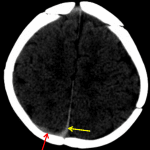

- Thin hyperdense collection overlying the posterior right parietal lobe and posterior interhemispheric falx, concerning for acute subdural hematoma

- Thin CSF density collection overlying the right frontal convexity, which may represent a chronic subdural hematoma vs hygroma

Thin hyperdense collection measuring up to 2 mm overlying the posterior right parietal lobe and posterior interhemispheric falx, concerning for acute subdural hematoma. No significant mass effect, herniation, or hydrocephalus.

Thin CSF density collection overlying the right frontal convexity, which may represent a chronic subdural hematoma vs hygroma.